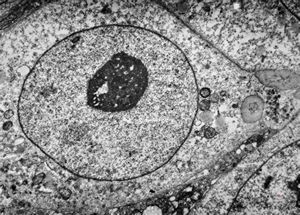

F,50y. | progressive multifocal leukoencephalopathy- viral particles in a glial cell